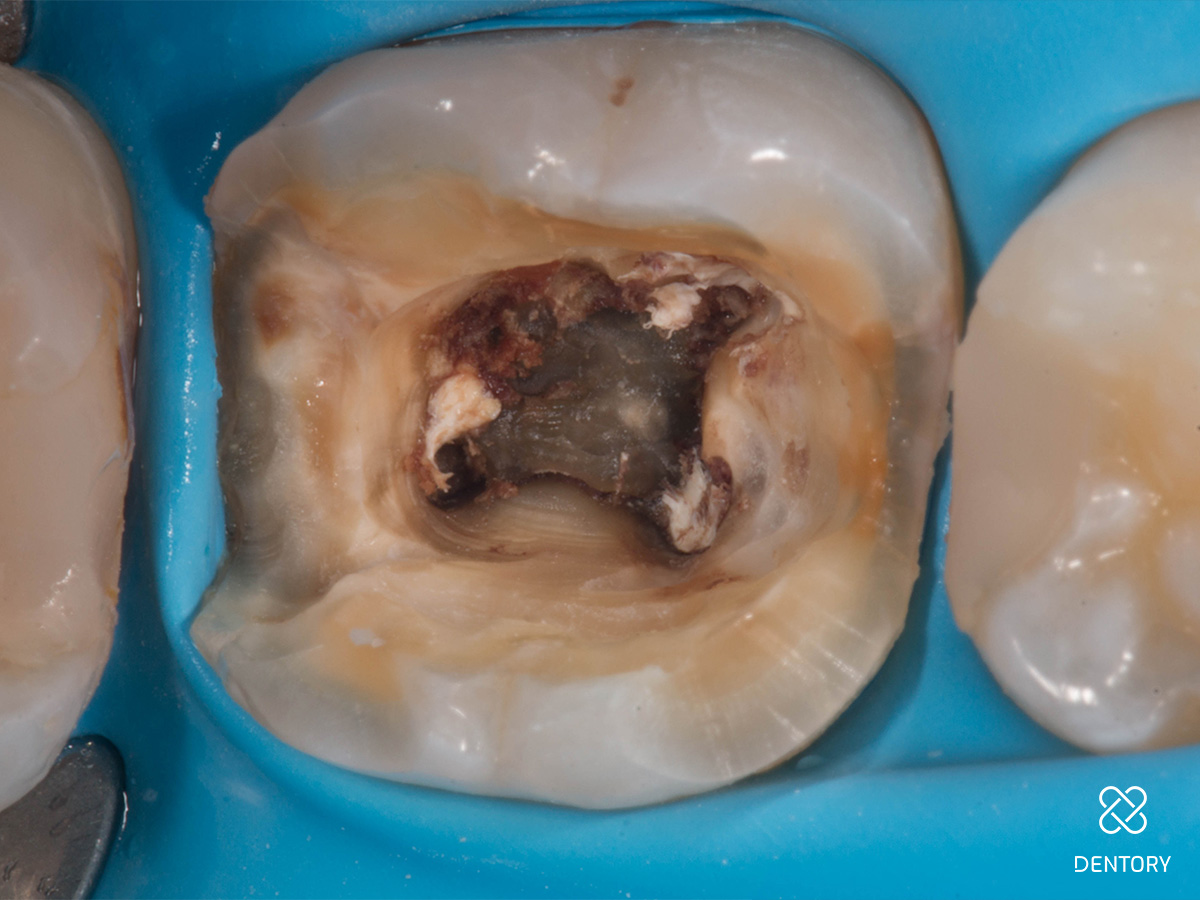

Abbildung 3

Initiale Zugangskavität: Mit einem Rosenbohrer wurde die alte Guttapercha reduziert. Für den Prä-Endo Aufbau wurden sowohl mesial als auch distal die Höcker partiell eingekürzt. Dies senkt das Frakturisiko bis zur indirekten Post-Endo Restauration.